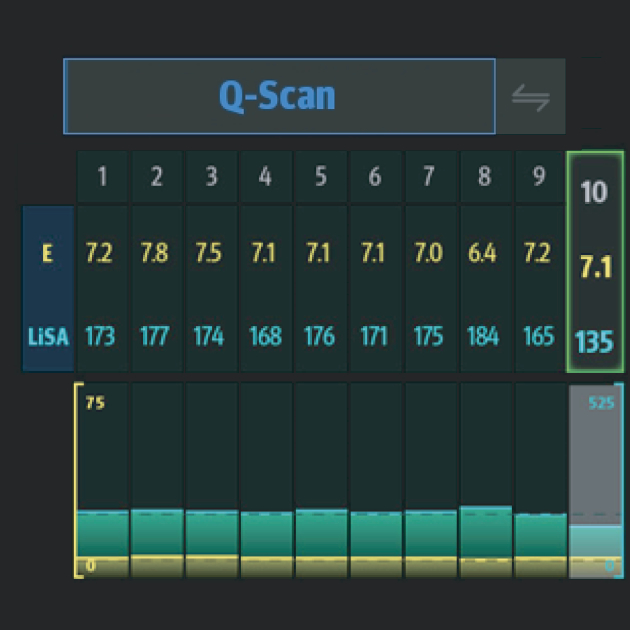

? ??? ?? ???? ???? ?? ???? Hepatus? ? ??? ??? ???? ??? ??? ?????. ???? ????? ??? ? ?? ??? ???? ????? ? ?? ???? ? ?? ??? ??? ??? ?????.

??? ???? ?? ? ??? ? ? ???? ?? ??, ??, ???? ? ?? ??? ??? ? ????. ?? ?? ???? ?????.